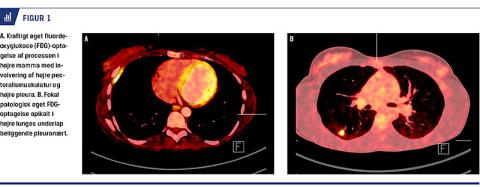

I august 2012 fandt man skyllevæsken fra processen i højre bryst polymerasekædereaktion (PCR)-positiv for Mycobacterium tuberculosis. En PET-CT viste dels inflammatoriske forandringer i højre hemithorax, dels en større absceslignende proces bag højre bryst (Figur 1A) og et område apikalt i højre lunge (Figur 1B) med konsolidering omkring en forkalkning. Processen gik gennem thoraxvæggen til brystet.